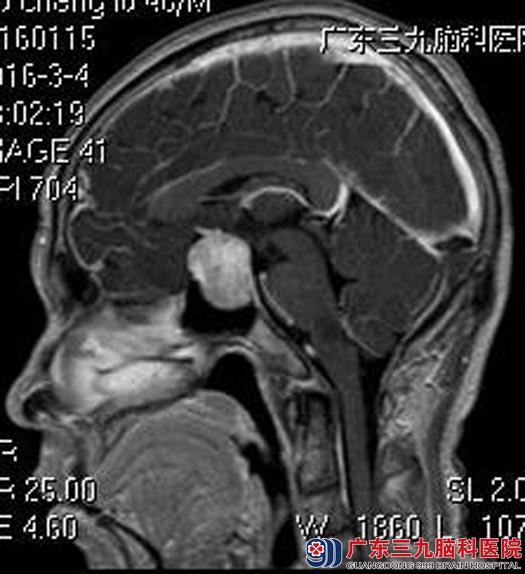

吴先生,45岁,一年前出现出现左眼视物模糊,颞侧为主,伴全身无力,一直在当地医院眼科就诊,治疗后症状稍有好转。二天前突然感觉有头晕不适,头部CT检查提示鞍区占位,考虑垂体腺瘤。

入住广东三九脑科医院垂体瘤诊疗中心,完善各项检查,由鲁明主任主刀在全麻内镜下经鼻行蝶鞍区垂体腺瘤切除术,进入蝶窦后,见鞍底完整。刮除窦内粘膜。导航再次定位,全层切开肿瘤膜,清除全部肿瘤组织,用脑膜补片修复鞍底。没有出现术后并发症,十天后即出院。

▲术前MR